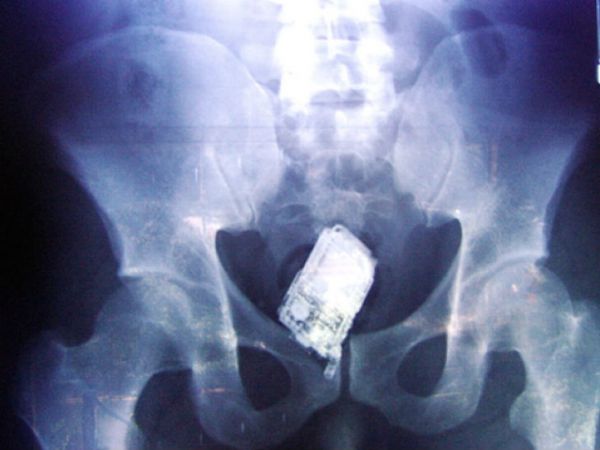

А еще заключенные глотают сотовые телефоны.